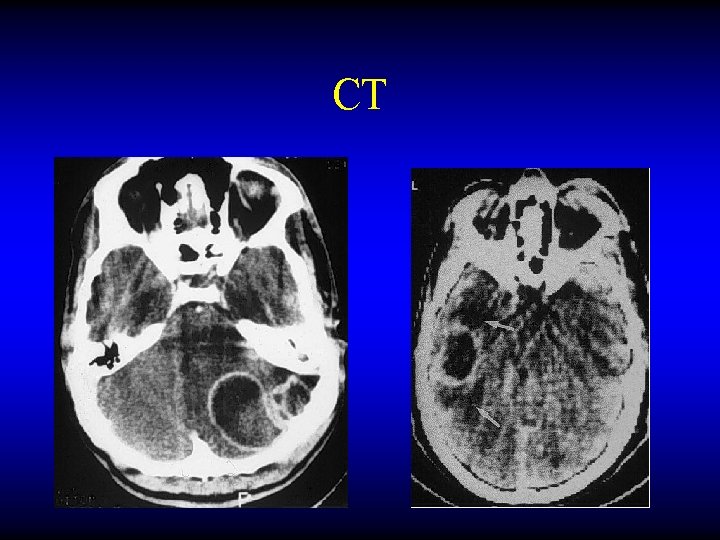

OTOGENIC BRAIN ABSCESS Diagnosis • • CT MRI LP Burr hole needling

CT